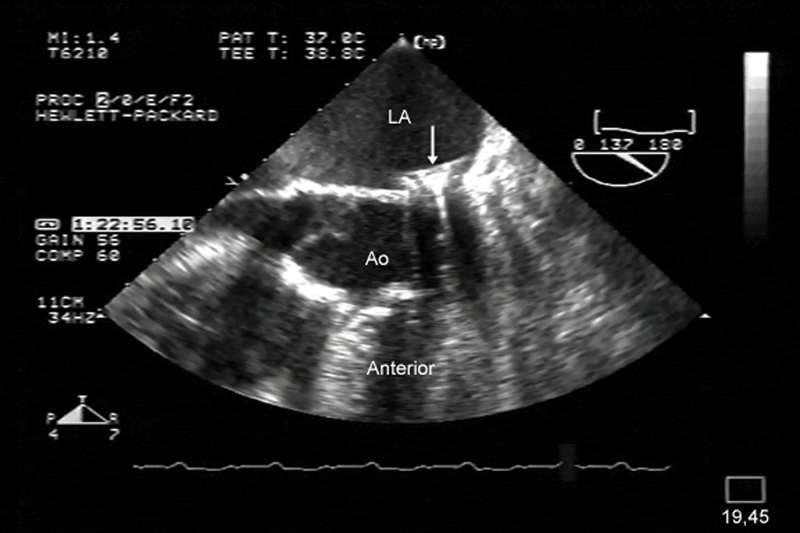

فحوصات تشخيصية لبعض امراض القلب والشرايين التاجية